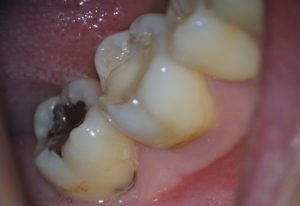

治療前

しみる歯をマイクロスコープで確認すると…

つめものが欠けているところが数カ所あり、これがしみる原因と考えられます。

歯の量が少なく、亀裂が入ってしまっているところも・・・

青丸:詰め物の欠け 赤丸:亀裂